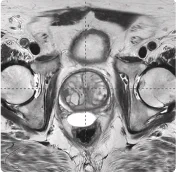

169 cc prostate post-MRI showing BioProtect Balloon Spacer, prostate, and rectum.

Post-MRI

Image courtesy of Dr. Vishesh Agarwal, Radiation Oncologist.